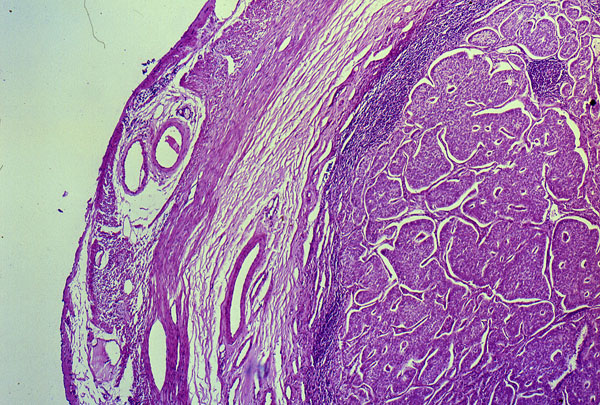

Carcinoid of the appendix, histology

The lumen of the appendix is obliterated by solid masses of uniform cells.